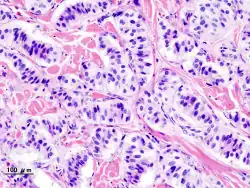

Obraz histopatologiczny insulinoma |

Guz insulinowy, wyspiak, insulinoma (łac. insulinoma) – nowotwór wywodzący się z komórek B wysp trzustkowych, wytwarzający insulinę, w związku z czym głównym jego objawem jest hipoglikemia.